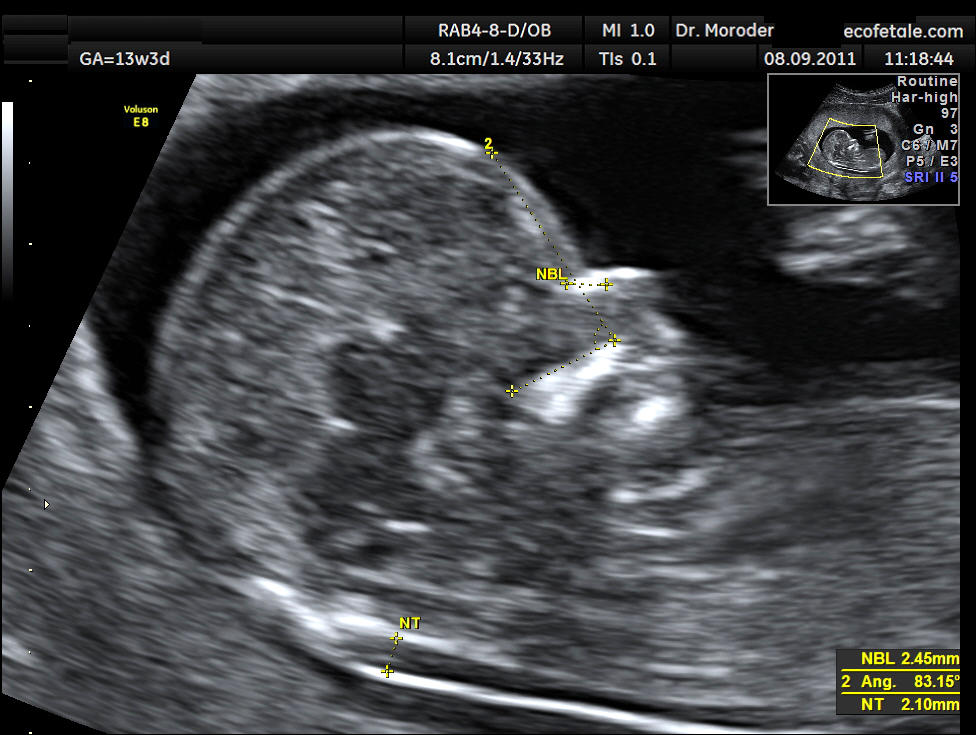

Il test della translucenza nucale è un esame di screening prenatale tra i più diffusi, che viene condotto nel primo trimestre, tra le 11 e le 13+6 settimane di gestazione.

Consiste in un’ecografia nel corso della quale si misura lo spessore della cute del feto a livello del collo. La presenza di uno spessore aumentato è associato a un’aumentata probabilità di sindrome di Down.

Al fine di ottenere i migliori risultati occorre un apparecchio ecografico di ultima generazione ed un operatore specializzato, che abbia seguito con successo il corso tenuto dalla “The Fetal Medicine Foundation”. Una volta effettuate le misurazioni, attraverso un software specifico si calcola la percentuale di rischio, che viene paragonata a quella specifica dell’età materna.

Una translucenza nucale che risulti sensibilmente aumentata (valori superiori a 3.5 mm) può essere indicativa anche di patologie e condizioni di diverso tipo, come malformazioni cardiache e rare sindromi genetiche; in questo caso si effettuerà quindi anche uno studio accurato dell’anatomia cardiaca attraverso un’ecografia di secondo livello attorno alle 20 settimane.

By This Photo was taken by Wolfgang Moroder. Feel free to use my photos, but please mention me as the author and send me a message. This image is not public domain. Please respect the copyright protection. It may only be used according to the rules mentioned here. This specifically excludes use in social media, if applicable terms of the licenses listed here not appropriate.Please do not upload an updated image here without consultation with the Author. The author would like to make corrections only at his own source. This ensures that the changes are preserved.Please if you think that any changes should be required, please inform the author.Otherwise you can upload a new image with a new name. Please use one of the templates derivative or extract. – Own work, CC BY-SA 3.0, Link